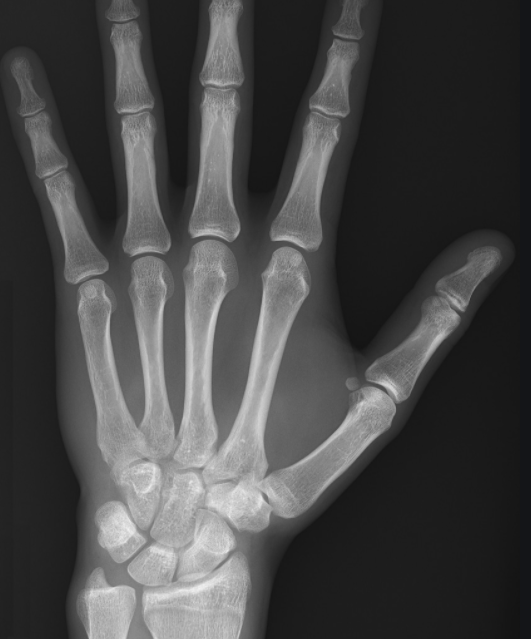

전리방사선 및 비전리방사선의 취급과 방사성동위원소를 이용한 행의학검사와 초음파검사 등 관리 및 취급 업무를 하는 사람을 말합니다. 보통 병원에 가서 엑스레이 검사를 하거나, CT, MRI 검사를 하는 사람들이 방사선사이고, 핵의학과, 방사선종양학과에서 일하는 사람도 방사선사입니다.